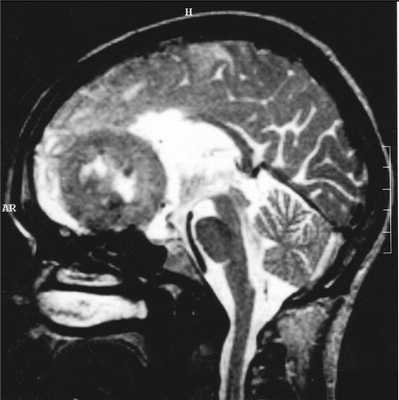

МРТ головного мозга. Менингиома свободного края намета мозжечка (область шишковидной железы). Сагиттальные Т1-зависимые МРТ до и после контрастирования.